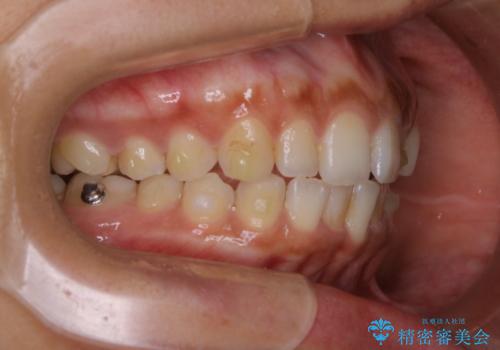

- インビザライン(マウスピース矯正)の治療中にステインが気になり、クリーニング希望とのことでした。

アタッチメントの周囲などに、ステインの付着や、プラークがみられたためPMTC(自費クリーニング)30分コースを行いました。

矯正治療中は、虫歯や歯周病のリスクが高くなったり、長い時間マウスピースを着用することにより、ステイン(着色)がしやすくなることがあります。

そのため矯正治療中は、(マウスピース矯正・ワイヤー矯正共に)クリーニングを行い、こまめに汚れを取り除き、お口のケアをすることが大切です。